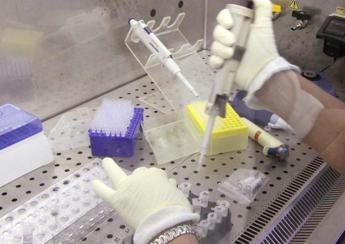

Covid, cariche di nitroglicerina sul virus: allo studio ‘farmaco bomba’

(Adnkronos) – Un nuovo antivirale allo studio negli Usa riveste Sars-CoV-2 di una sostanza chimica simile all’esplosivo nitroglicerina. E quando il virus prova a invadere l’organismo, una parte di questa ‘carica’ modifica temporaneamente la porta d’ingresso del coronavirus nella cellula bersaglio (il recettore Ace2), sbarrandola. A progettare questo ‘farmaco bomba’ – denominato per ora Nmt5 […]